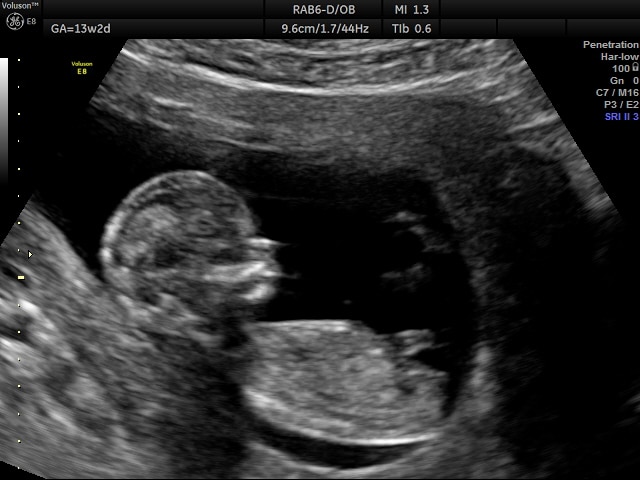

Een 2D echo is de meest gebruikte vorm van echoscopie tijdens de zwangerschap. Je ziet je kindje in duidelijke zwart wit beelden, waarbij vormen, bewegingen en het kloppende hartje goed zichtbaar zijn. Deze echo geeft vaak veel geruststelling en is een waardevol moment om bewust stil te staan bij je zwangerschap.

Korte 2D geslachtsbepaling echo vanaf 13 weken

Ben je 13 weken of verder zwanger en benieuwd of je een jongen of een meisje verwacht? Met een korte 2D geslachtsbepaling echo kunnen we vanaf 13 weken zwangerschap het geslacht vaak betrouwbaar vaststellen.

Tijdens de uitgebreide 2D echo nemen we ruim de tijd om je kindje te bekijken. We laten je zien wat we zien en benoemen organen en structuren, zodat je het beeld beter leert begrijpen. Je ziet bijvoorbeeld je baby bewegen, slikken, gapen of op een duimpje zuigen.